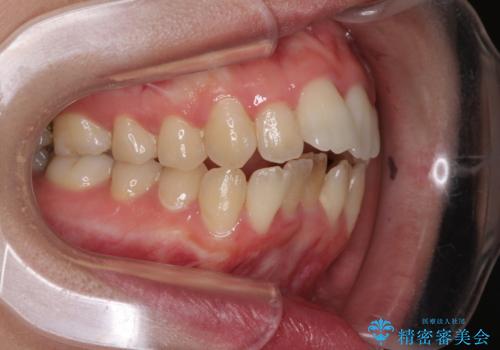

Eラインを改善したい ハーフリンガルによる抜歯矯正

- 口元の突出感を気にして来院された患者様です。

上下左右の第一小臼歯4本を抜歯して口元を下げる治療計画としました。